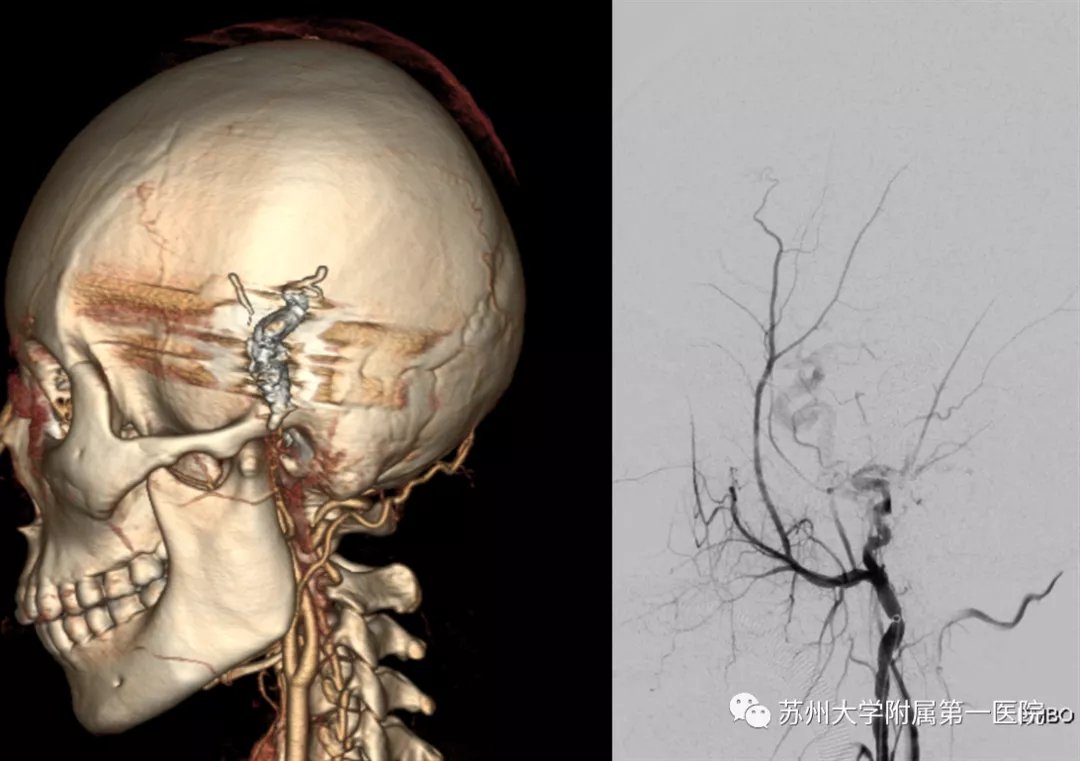

图为患者术前CT血管造影查(CTA),右图为术前DSA血管造影检查;黑色箭头为扩张、迂曲的异常引流静脉